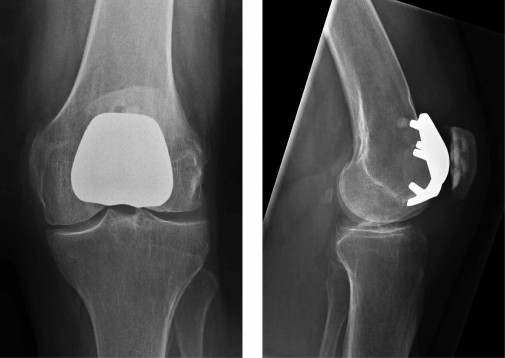

What does this x-ray show?

Patellofemoral arthroplasty: Prosthesis of patellofemoral compartment